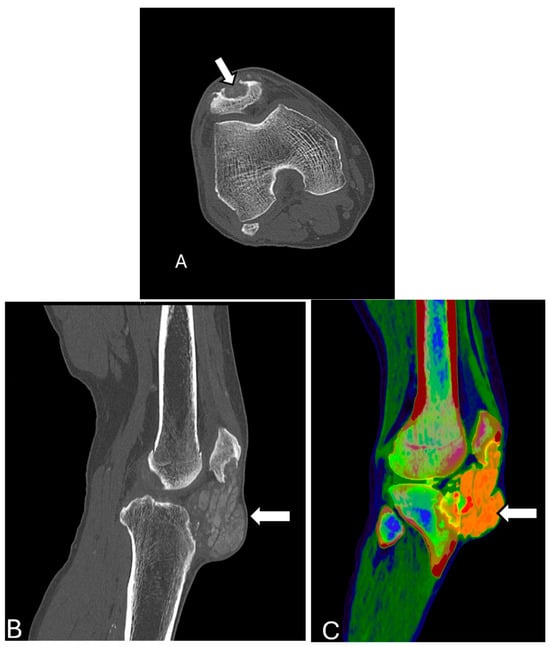

3.10. Metabolic Diseases